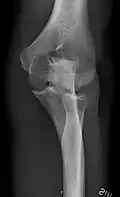

AP and lateral elbow X-ray

• Elbow - AP and Lateral. Radial head projections available on request

• Ankle - AP/Mortice and Lateral